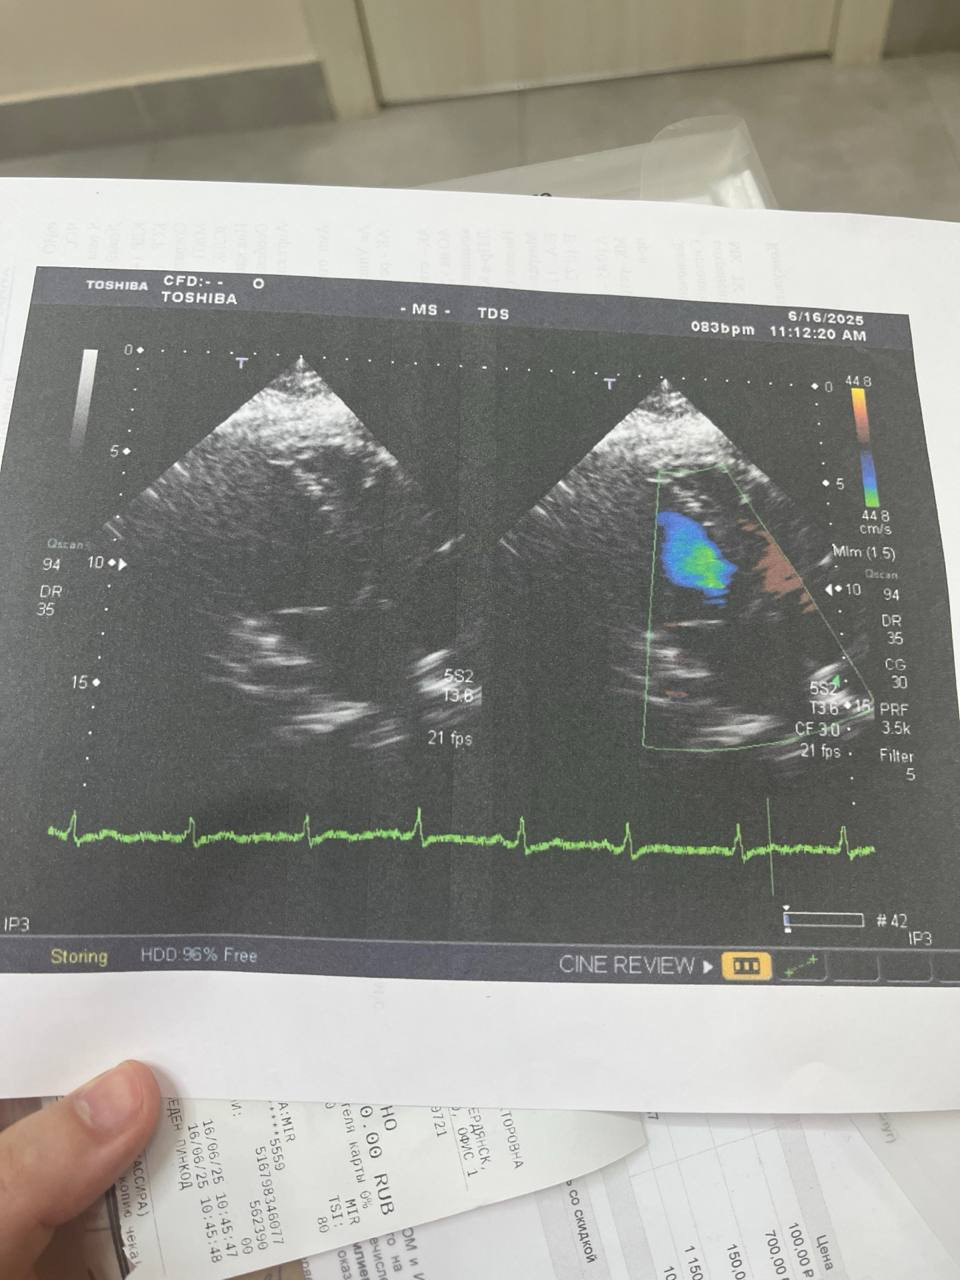

С болью в сердце я обратилась к кардиологу в частную клинику, она направила меня на узи и на анализы, анализы все в норме кроме инсулина, мои показатели 32,5  и на узи сердца у меня был поставлен такой диагноз мк, тк - функциональный ретроградный поток. Выписала мне таблетки корвадилол 100мг по 1/2 пить каждый день. Сердце как болело так и болит, рука левая может неметь, я очень переживаю что может случится инсульт или инфаркт. Подскажите пожалуйста что делать?

Здравствуйте. Ваши жалобы нельзя оставлять без внимания. Функциональный ретроградный поток на клапанах часто бывает вариантом нормы, но постоянные боли в сердце и онемение руки требуют дообследования это ЭКГ, суточное мониторирование, консультация невролога и эндокринолога (учитывая повышенный инсулин). Не откладывайте визит в крупный кардиологический центр или государственную клинику т.к нужно исключить ишемию и нарушения ритма. Самостоятельно увеличивать или отменять карведилол нельзя.